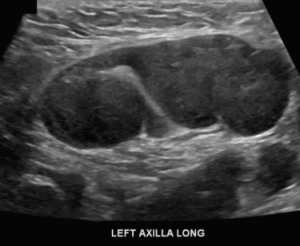

The mammogram is reviewed, and besides the abnormal lymph nodes, no other suspicious finding is seen in the breasts. An ultrasound is performed of the axilla:

Explanation: There are multiple abnormal lymph nodes in the left axilla, and so far no evidence of any abnormality in the left breast. The presence of unilateral axillary lymphadenopathy must be presumed to be metastatic breast cancer until proven otherwise. These findings must be deemed suspicious and biopsy of one of the lymph nodes should be performed. Whenever possible, the BI-RADS assessment and recommendation should be concordant.